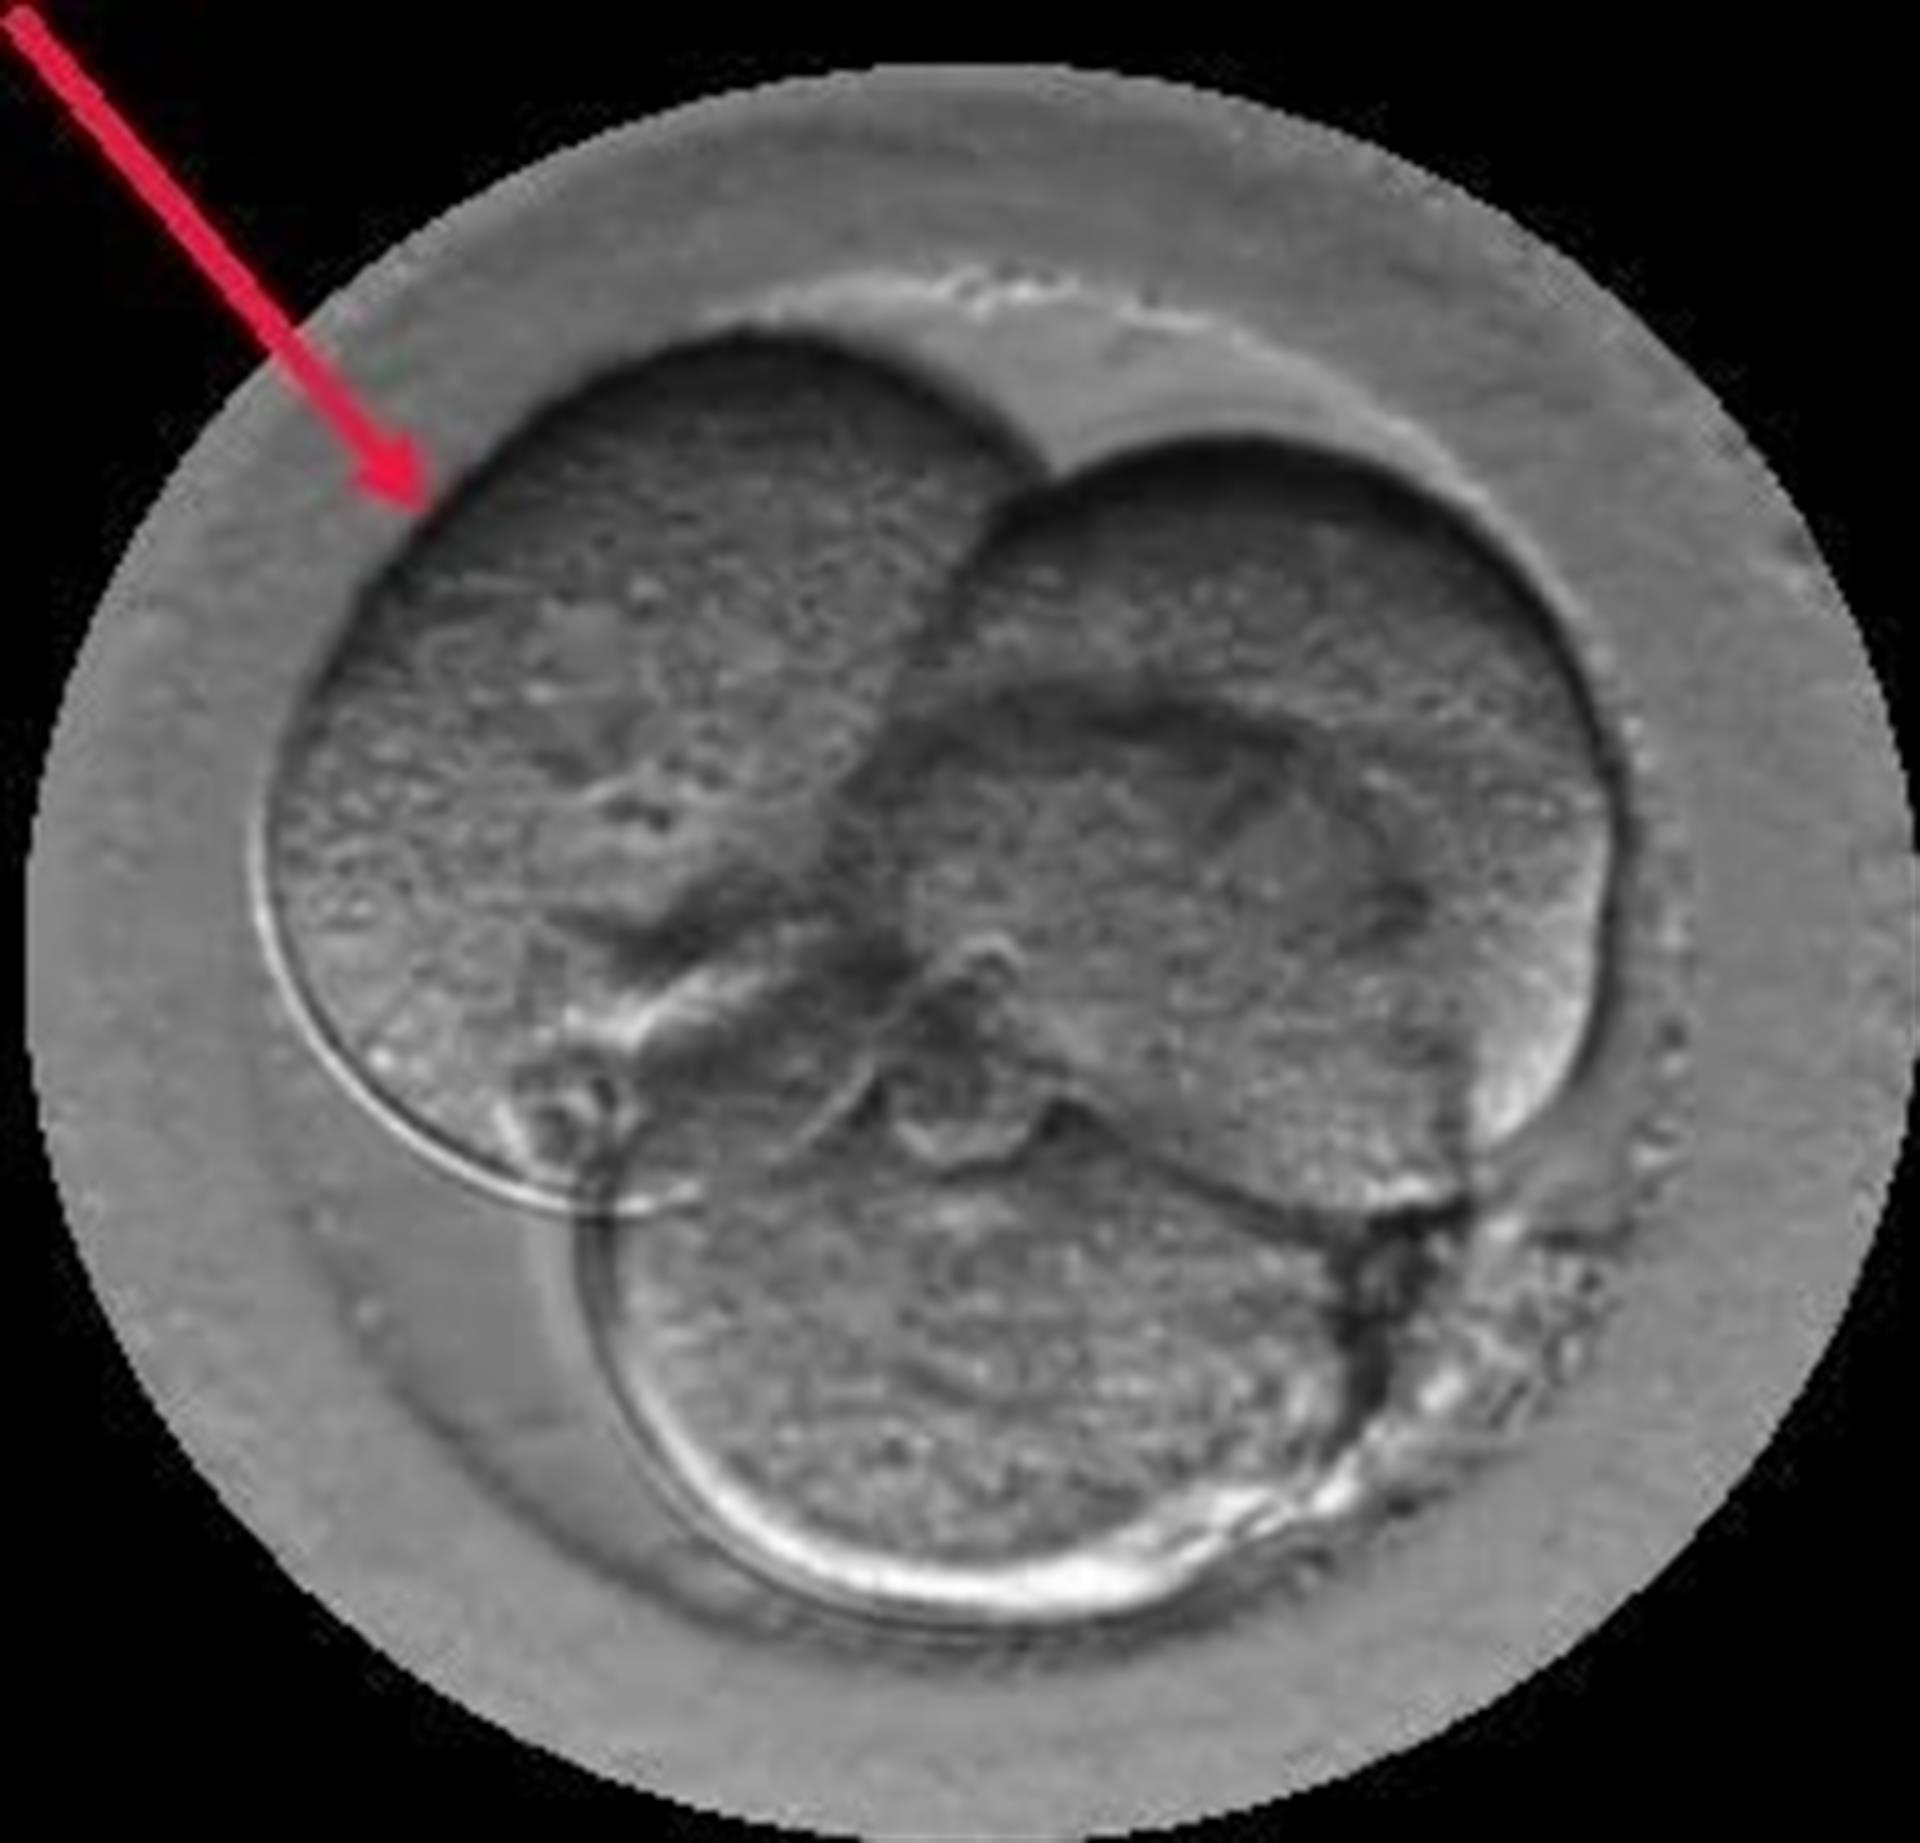

El Dr. Borja Marquès es el autor del estudio “Signos de auto-reparación de los embriones en el laboratorio de FIV” cuyas conclusiones apuntan que los embriones poseen un mecanismo de auto-corrección ignorado hasta hoy. Según este trabajo que se presenta esta semana en Murcia, en el 36º Congreso de la Sociedad Española de Ginecología (SEGO), embriones que han sufrido división reversa (desaparición de alguna de sus células) o multinucleación (presencia de dos o más núcleos en alguna de sus células) pueden acabar con éxito, es decir, con un embarazo normal y el nacimiento de un bebé sano.

Gracias a los incubadores con cámaras time-lapse (Embryoscope), en los laboratorios de Institut Marquès ha sido posible captar las imágenes de embriones con división reversa reabsorbiendo sus propias células y de embriones multinucleados expulsando las células anómalas en el 4º o 5º día de vida. Para conseguirlo, se ha analizado el desarrollo de 21.274 embriones, desde su fecundación hasta que llegaron a blastocisto.